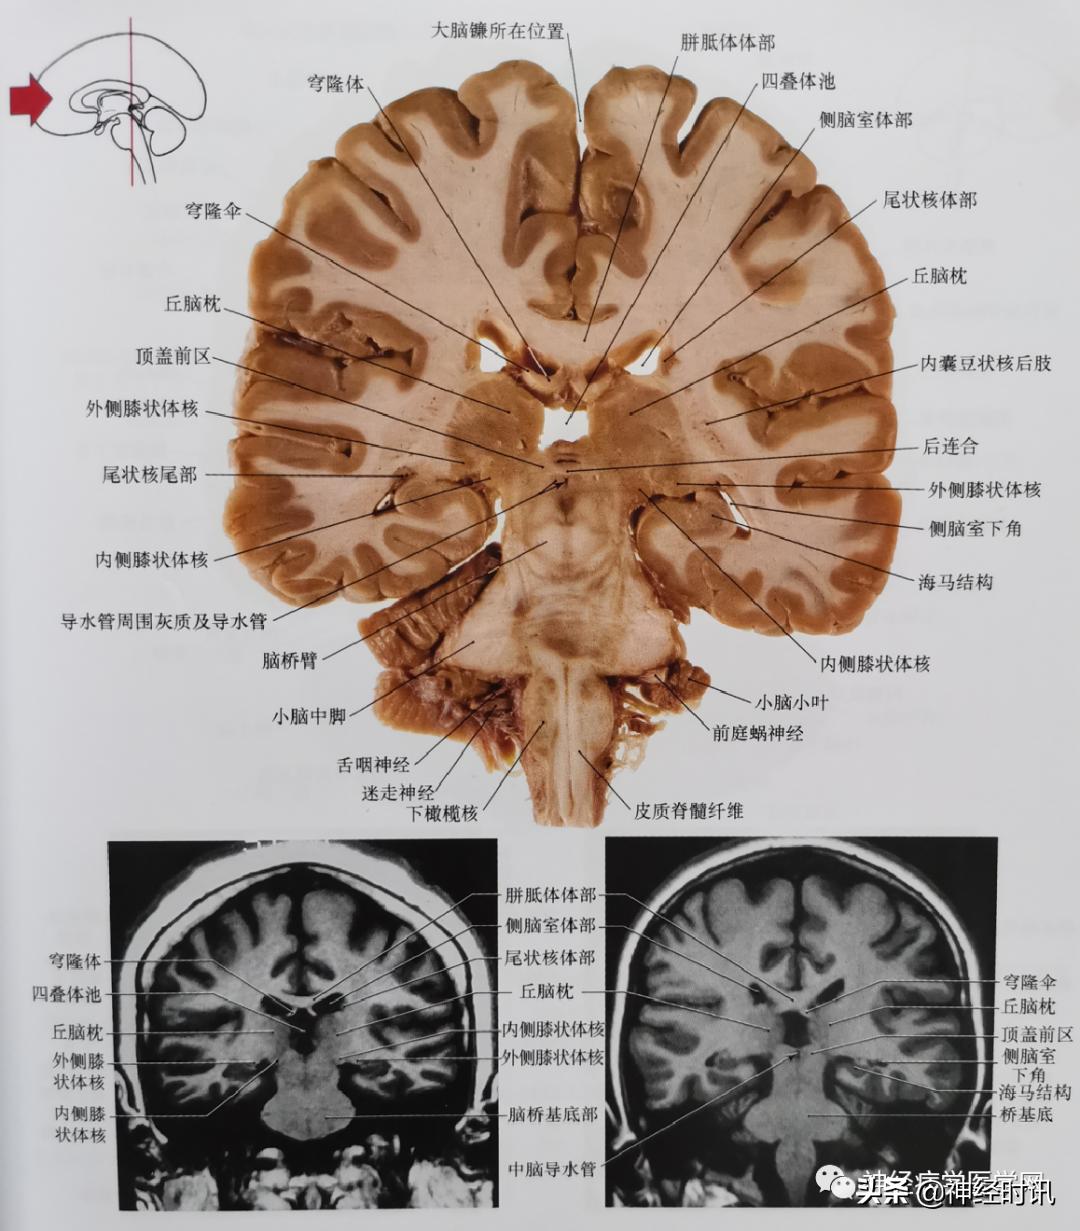

图5 通过丘脑腹外侧核尾部、中间块、丘脑腹后外侧核、红核、黑质、脑桥基底平面的冠状位影像。此平面儿完美地显示了内囊的纤维(切片中的内囊后肢)穿过大脑脚,进入桥基底(切片及磁共振影像可见);这些通过大脑脚的纤维,包括皮质脊髓纤维、皮质脑桥纤维(顶桥、枕桥、颞桥、额桥)及皮质核束纤维。

图6 通过丘脑枕核、内外侧膝状体核、中脑和脑桥被盖及延髓腹侧平面的冠状位影像。通过内囊后肢、大脑脚和桥基底皮质脊髓纤维正好定位于延髓的椎体部位。注意四叠体池的位置与第三脑室有显著的不同。在大脑切片与MRI影像均显示膝状体特征性地位于丘脑枕的下方。